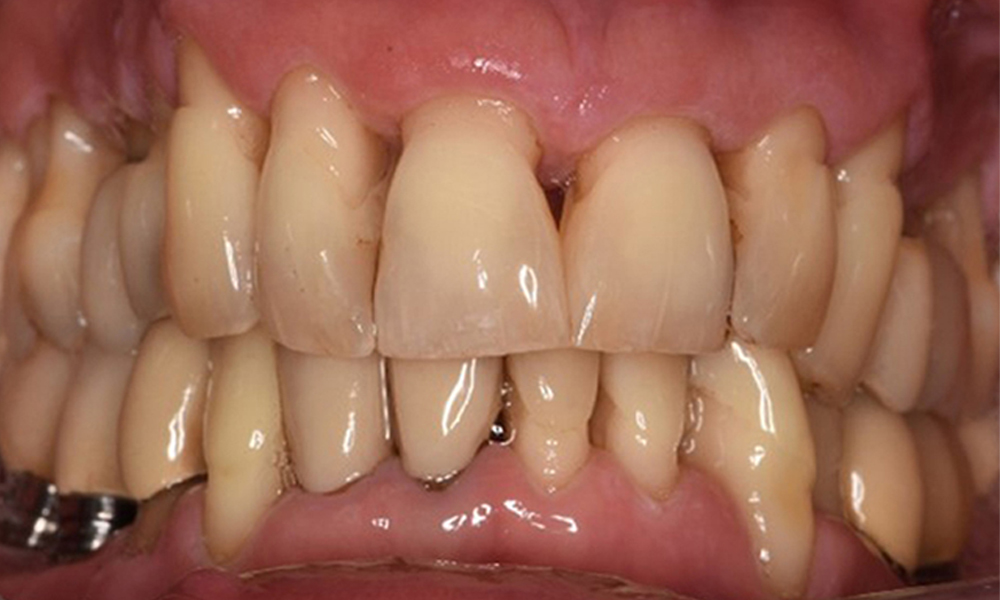

Хигиената на устната кухина и сътрудничеството от страна на пациента са много добри (виж снимката „изглед отпред“). Необходими са само повтарящи се инструкции и мотивация за поддържане на орална хигиена.